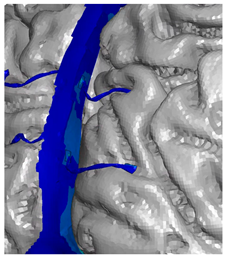

| Frontal veins |  |  |  |

| Parietal veins |  |  | |

| Occipital veins |  |  |